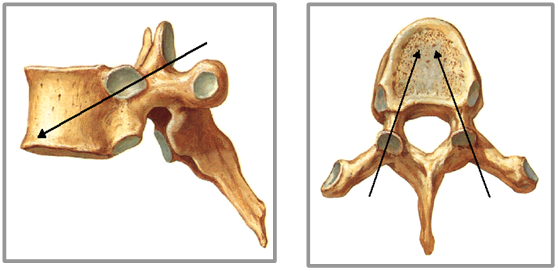

PKP入路有三类:

• 经椎弓根(推荐)

• 经椎弓根外

• 椎体侧方

经椎弓根外途径:一般为胸椎穿刺途径。进针点位于横突和上关节突交界处,在肋横关节间稍高于椎弓根外侧壁。

经椎弓根途径,一般为胸腰椎穿刺途径,建议适于T6以下(视实际椎弓根粗细而定),可有效避免血管神经损伤,有效防止填充剂向椎旁渗漏。进针方向为2点钟,15~20度角。

进针方向 ⬇

进针点-外上象限 ⬇

进针点 ⬇

特殊情况下的穿刺方向 ⬇

进针过程  三个关键点 ⬇